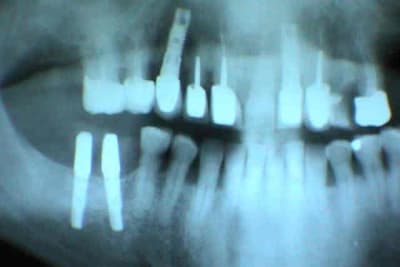

1er cas: une belle réussite chirurgicale et un massacre prothétique

2ème cas: une belle réussite prothétique(aucune mobilité, esthétiquement acceptable malgré la position des implants) et un massacre chirurgicale (6 ans)

C'est des implants zygomatiques sur ton premier cas ?

et 1 orbiculaire

désolé orbitaire

à nmon avis l'implant est "orbitaire" en raison d'une déformation de la pano (patient un peu de travers)

2 précisions:

je n'ai rien fait au patient: il voulait un avis sur son état actuel

l'implant est bien sous l'orbite

inconscience ou non?